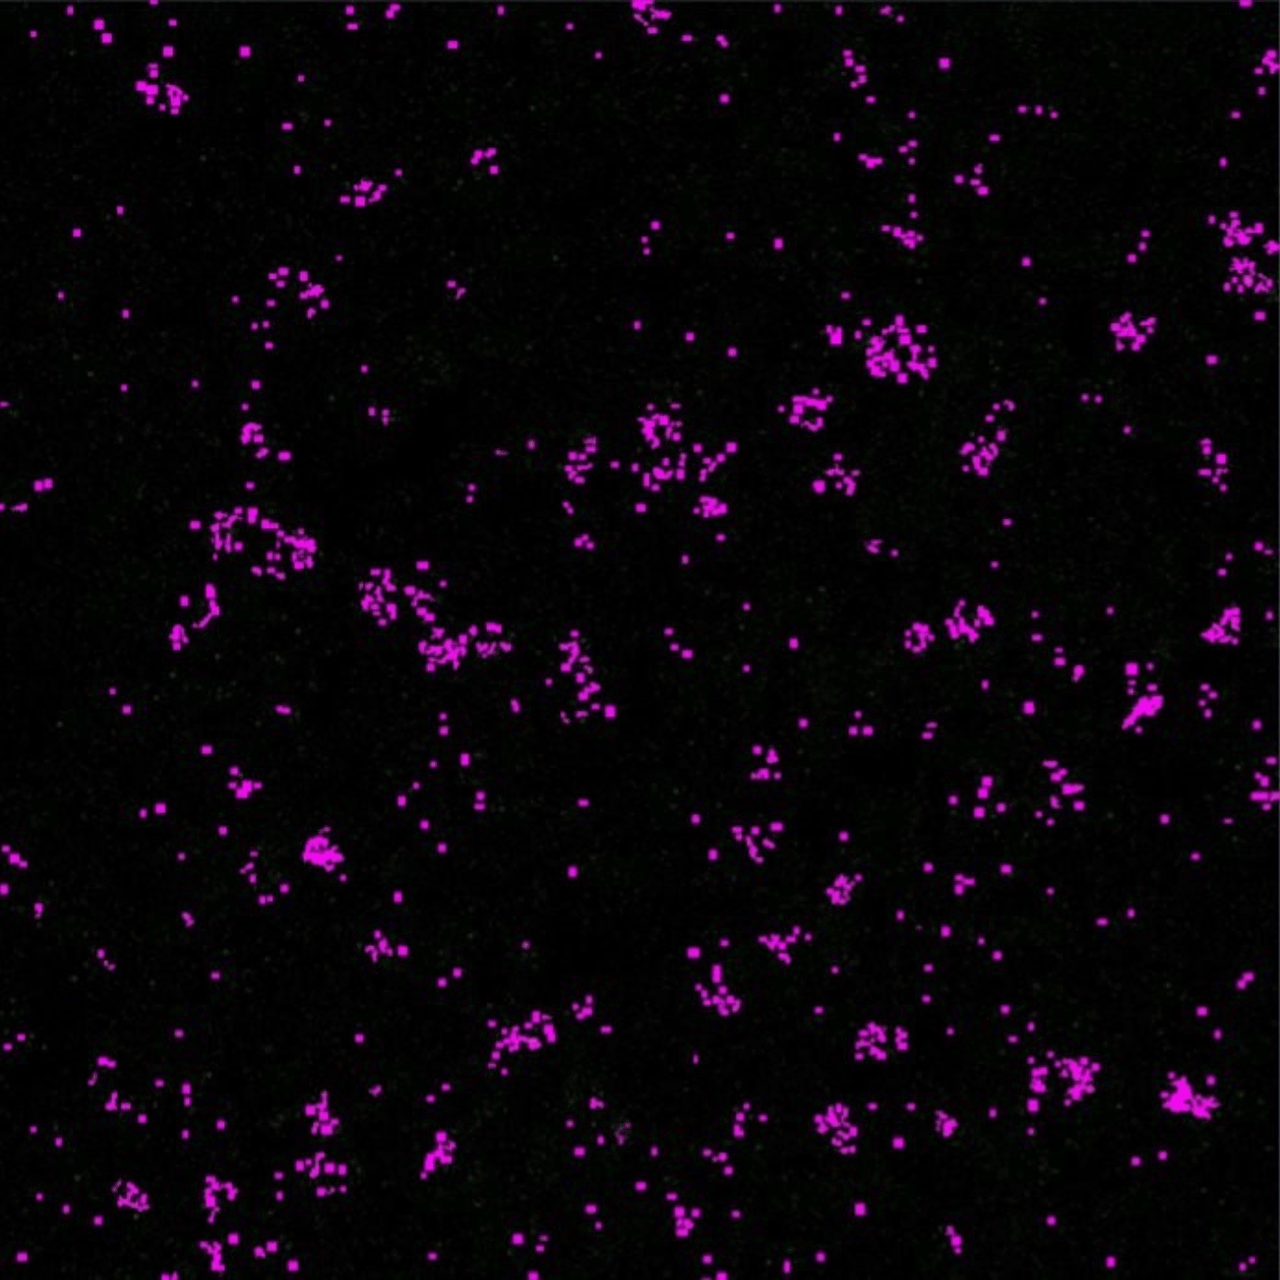

• Figure 5A: CD8A gene expression analysis using Bio Apps spot detection.

A. Raw data of CD8A expression

Figure 5A: CD8A gene expression analysis using Bio Apps spot detection.

Beyond simple visualization, spatial analysis tools provide powerful methods for quantifying cellular interactions. ZEISS Bio Apps Spot Detection app simplifies the identification of mRNA transcripts aggregated with automated segmentation analysis within the ZEN environment. In this case study spot analysis allows for precise measurement of gene expression within specific regions of interest, revealing localized variations in transcript abundance.